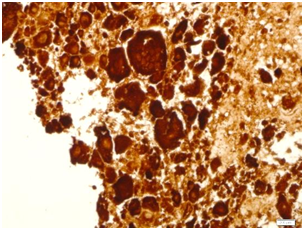

A specimen labeled as left frontoparietal hematoma - ? cavernoma from a 41 year old non-hypertensive female patient on ventilator was received for histopathologic examination. The patient was transferred from outside hospital to neurosurgical department of our hospital for craniotomy and evacuation of intracerebral hematoma. The clinoradiologic diagnosis was spontaneous intracerebral hematoma with intraventricular extension with normal ventricle, probably due to cavernoma. The microscopic examination of the specimen revealed extensive hemorrhage with peripherally placed mono-nucleated and multinucleated atypical cells. The mononucleotide cells were medium to large size with abundant cytoplasm and central large hyperchromatic nuclei. The multinucleated cells were large with abundant eosinophilic cytoplasm and hyperchromatic multinucleated bizarre nuclei. They were considered as cytotrophoblasts and syncytiotrophoblasts respectively (Figure 1-4). Immunohistochemistry showed that the atypical cells were CKAE1AE3 +, HCG+, GFAP-, CD31- and Vimentin- (Figure 5 to 10). A thin rim of GFAP positive glial tissue was seen in one fragment. Based on these findings, a diagnosis of metastatic choriocarcinoma was made. The patient survived the surgery and started recovering neurologically, but chose to go back to her own country for further management. So, we could not get any details of her obstetric history or previous medical illness.

Figure 5 CKAE1AE3.

Figure 6 CKAE1AE3.

Surgically resected blood clots from intracerebral hemorrhage (ICH) for histopathological examination are the frequent samples from neurosurgical department. Intracerebral hemorrhage has a number of causes, including: hypertension, head trauma, arteriovenous malformation, cavernoma, ruptured cerebral aneurysm, primary or metastatic neoplasm, bleeding disorder and medication. Incidence of bleeding is more in metastatic tumor than primary tumor.1 Most common metastatic tumors known to cause intracerebral hemorrhage are choriocarcinoma, bronchial carcinoma, melanoma and renal cell carcinoma. In our case, on H&E examination, histopathologic differentials were metastatic choriocarcinoma, metastatic sarcoma and symplastic cavernoma/hemangioma. Cytokeratin positivity and negative vimentin ruled out possibility of sarcoma, negative CD31 ruled out hemangioma and positive HCG (with positive cytokeratin) confirmed metastatic choriocarcinoma.4 Serum/CSF beta-HCG ratio will be decreased in metastatic intracerebral choriocarcinoma,5 In this case, Serum/CSF beta-HCG ratio and other investigations could not be done as it was an unsuspected case transferred from outside hospital in critical condition and the patient went back to her own country for further management. The choriocarcinoma is a rare highly malignant vascular trophoblastic tumor with high incidence of metastasis. The most common sites for metastatic choriocarcinoma are lung, brain and liver. Rarely, it can metastasize to gastrointestinal tract, kidney, spleen, genital tract and lymph nodes.